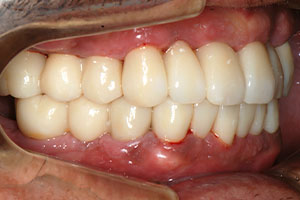

치료증례 전후사진

Before & After